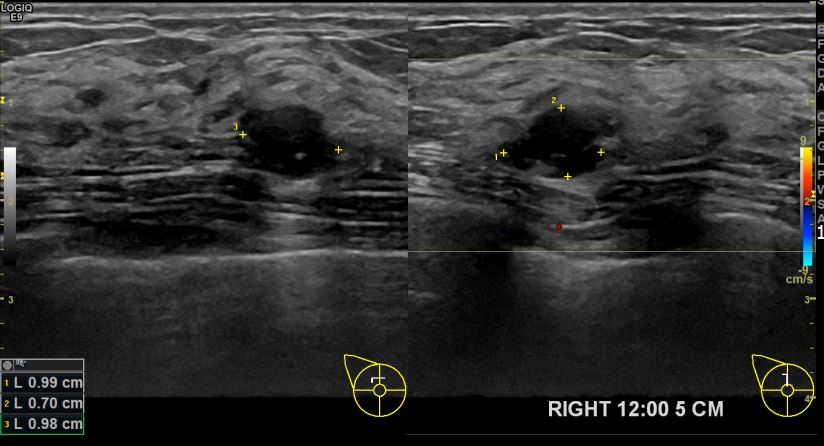

아산유외과개원후 703번째 유방암진단

상기환자 우측 12시방향 3개월 경과관찰하신 50대 여성분으로 크기가 자라나 조직검사시행후 유방암진단되었습니다.